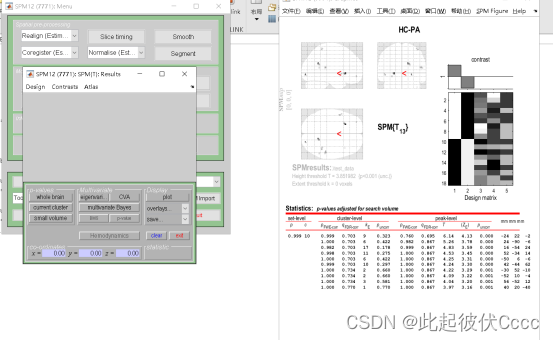

5.出现结果

6.将结果保存,点击Save->threshold SPM,之后再给文件取名字回车即可